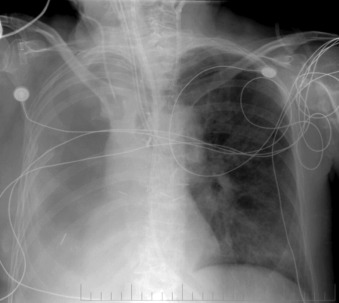

Central Venous Lines ( Figs. 22-1 to 22-13 )

To avoid mechanical irritation (from the catheter tip) and chemical irritation (from infusate) of the right atrium, the catheter tip of a central venous line should be further than the junction of the internal jugular vein and subclavian veins (near the level of the first thoracic rib). In addition, the tip should not be further in than the junction of the superior vena cava and right atrium. Central venous catheters that are intended to record central venous pressure should lie distal to the last venous valves (in the subclavian and internal jugular veins, 2.5 cm proximal to the beginning of the brachiocephalic vein) and before the right atrium. The ideal position of the tip of a peripherally inserted central catheter (PICC) line is in the distal superior vena cava.